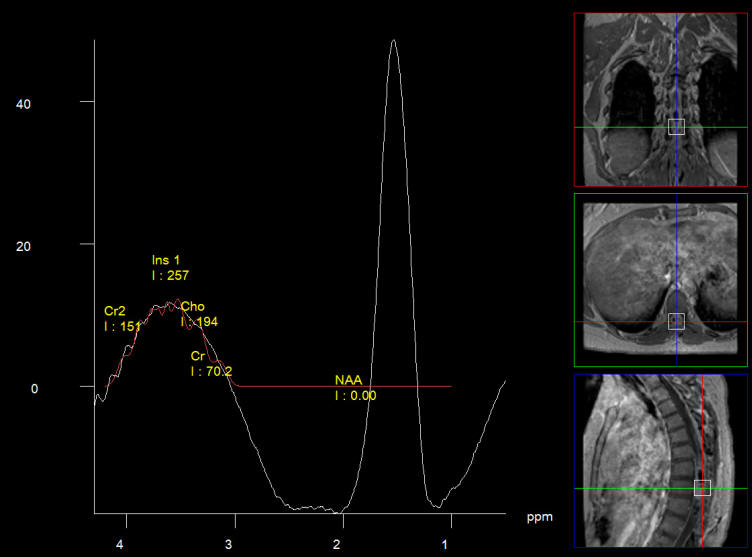

MRI of the dorsal spine with contrast and myelography and fibertraking and spectroscopy showing the recent lesions as seen in the below pictures with abscess formation.

MRI showing the new flare with abscess malformation and the old one

Fibertraking of the spinal cord at the lesion showing some scanty fibers ready for attack from behind (The middle picture)

Spectroscopy confirming the tbc abscess nature of the flare. High lipid and the choline is due to contamination of the voxel.